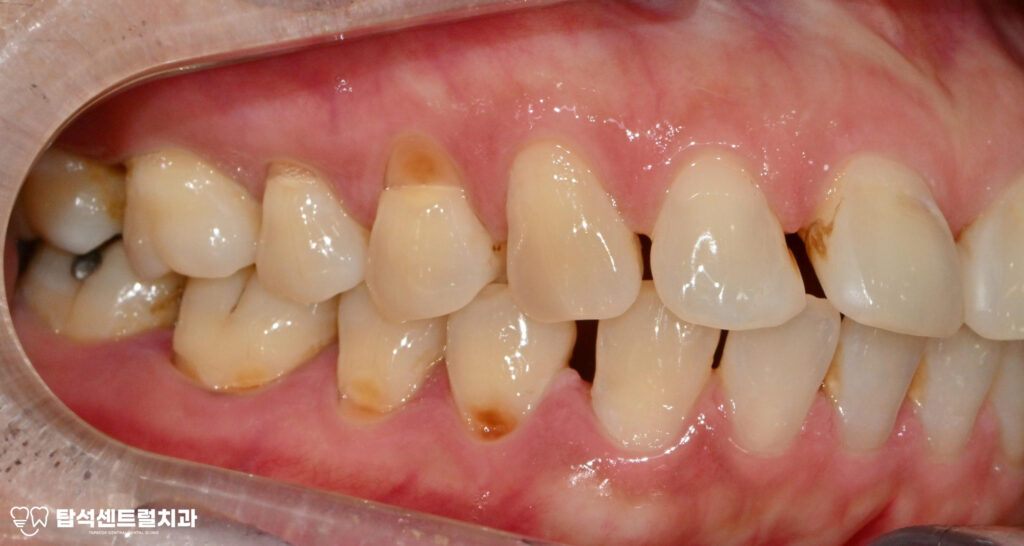

왼쪽 위 아래 어금니에서

통증이 느껴진다면 잇몸 염증을

의심해볼 필요가 있습니다.

특히 음식을 먹을 때 불편함이

지속되거나 이가 흔들리는

느낌이 든다면, 치주 질환이

꽤 오랫동안 진행되어왔을

가능성이 높습니다.

다수 치아에서 나타난 치경부 마모증은

레진으로 수복하는 것이 적절합니다.

치경부 마모증은 치아 목 부분이 닳아서

움푹 파인 상태를 말하며,잘못된 칫솔질이나

이갈이 습관으로 발생합니다.